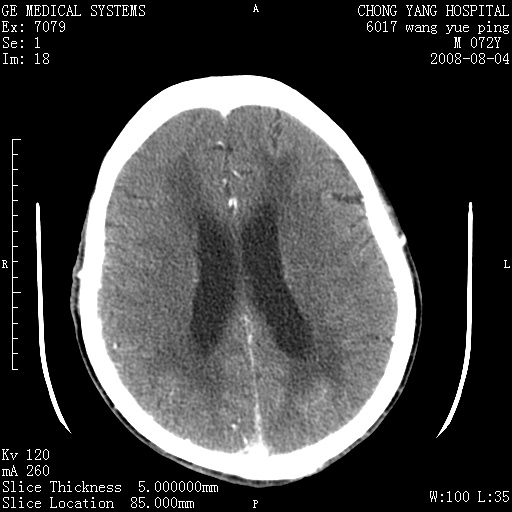

标题: CT14987:M72Y,头痛头昏,BP220/110. [打印本页]

标题: CT14987:M72Y,头痛头昏,BP220/110.

1)考虑左侧小脑脑梗塞。2)脑白质病。3)脑萎缩。4)双侧鼻腔新生物(息肉?)并阻塞性副鼻窦炎。

1.左侧小脑大面积梗塞;2.左侧基底节区腔梗;3.白质疏松;4.脑萎缩;5.慢性副鼻窦炎

小脑左侧病灶呈扇形分布,增强后未见明显瘤体样节结影,病变区未见强化。

支持:左侧小脑脑梗塞梗塞表现

另:脑白质病。脑萎缩。双侧鼻腔新生物(息肉?)并阻塞性副鼻窦炎。

1)考虑左侧小脑脑梗塞,建议治疗后复查除外其他,左基底节区腔隙性脑梗塞2)脑白质变性3)脑萎缩。4)双侧鼻腔新生物(息肉?)并阻塞性副鼻窦炎。